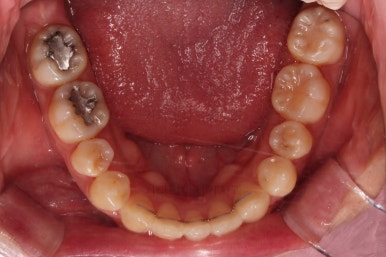

물론 다양한 이유로 아래 앞니를 발치하고 아랫니 3개로 마무리를 하는 경우도 굉장히 많지만 이번 환자분의 경우에는 여러 가지 의미로 마무리가 썩 좋지는 않은 것 같다는 생각이 들었습니다.

윗니는 좌측 작은 어금니가 한 개 모자랐고 아랫니는 앞니 하나가 모자라네요.

아랫니는 최대한 추가 발치 없이 후방의 송곳니를 당겨와서 앞니 역할을 하게 했습니다.(총 4개 앞니처럼)